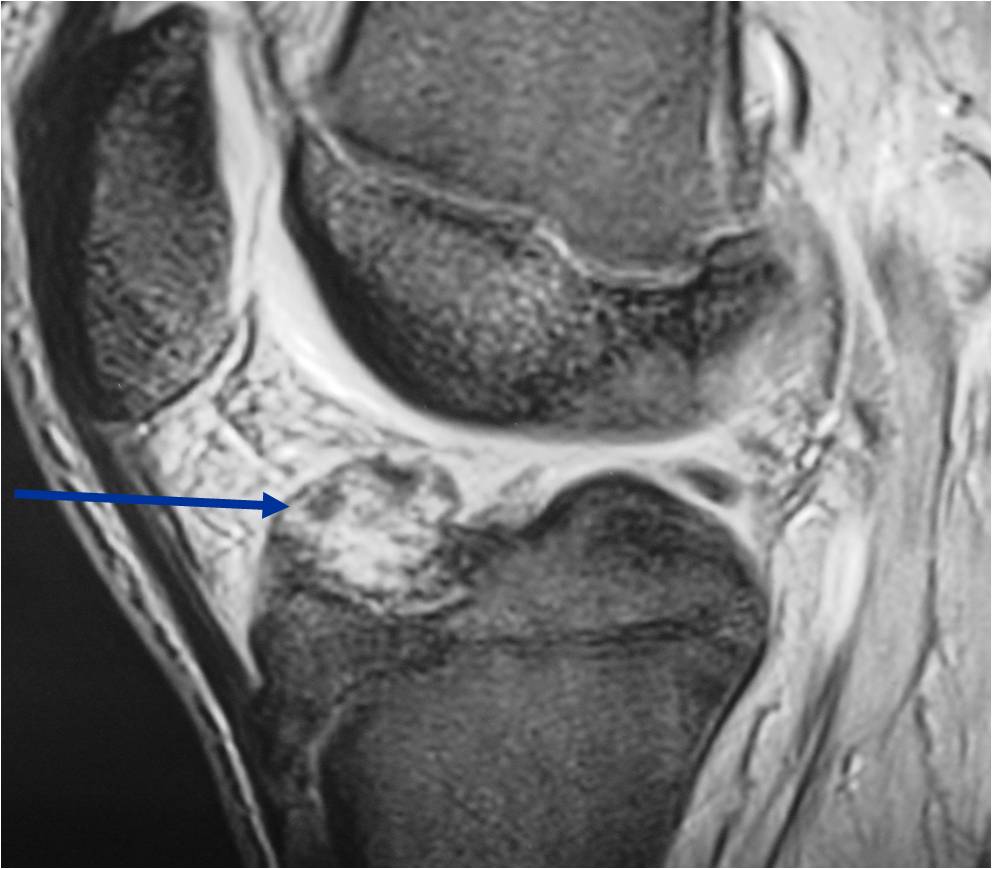

- (MRI appearance)

- Geographic, well circumscribed lesion in the epiphysis

- Intermediate Signal on T1

- High signal on T2 mixed with low signal areas (low signal areas proposed to be secondary to lysosomal content of highly cellular areas)

- Fluid/Fluid levels demonstrated in tumors that have undergone ABC change (aneurysmal bone cyst change)

- Extensive Surrounding edema is common

- Joint effusion in 30-50% of cases